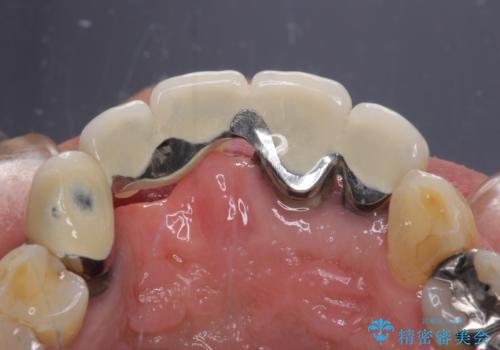

- 前歯のブリッジのせいで話しにくく、金属の縁などが露出して見栄えが悪いので、作り直したいとのことで来院された患者様です。

土台となる歯は根管治療の結果が良好ではないため、根管治療からやり直しをした後、オールセラミックブリッジにて補綴することとしました。